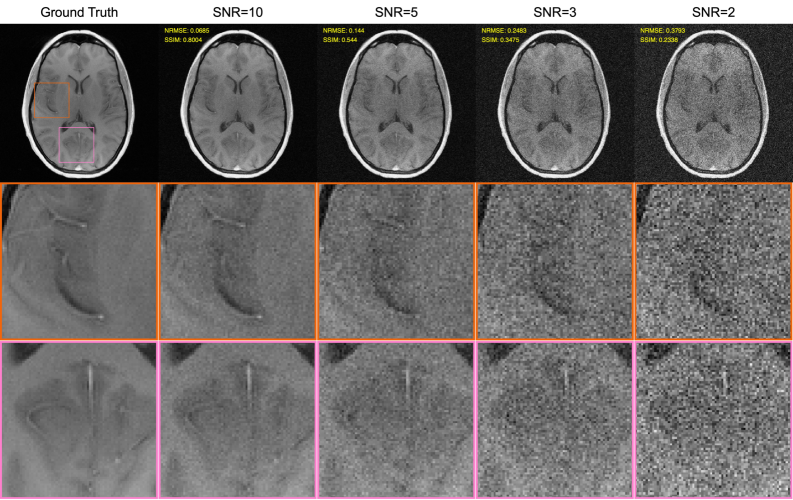

Figure 1: Illustrative examples of the different SNRs we considered, shown for a representative slice. The top row shows the ground truth image 𝐫tN0\mathbf{r}_{t}^{N_{0}}, as well as simulated noisy images that are obtained for high-resolution (N0×N0N_{0}\times N_{0}) sampling with uniform averaging w~0=8\tilde{w}_{0}=8 for different simulated noise levels. The images were obtained using simple inverse Fourier transform reconstruction of the averaged noisy data, followed by SENSE-based coil combination. We show normalized root-mean-squared error (NRMSE) and structural similarity (SSIM) metrics in the top left corner of each noisy image. The bottom two rows show zoom-ins to specific patches, with the patch locations marked in the ground truth image of the top row.

Our simulations explored four different noise levels: SNR = 2, 3, 5, and 10, representing denoising problems with varying degrees of difficulty as illustrated in Fig. 1. The target SNR levels were defined for images generated using conventional reconstruction – i.e., Fourier reconstruction with sensitivity-based coil combination. The simulated noise variance was selected to produce the desired SNR levels in the central white matter of typical brain slices, assuming a high-resolution acquisition (N0N_{0}=320) with uniform 8×\times averaging (i.e., w~0=8\tilde{w}_{0}=8).